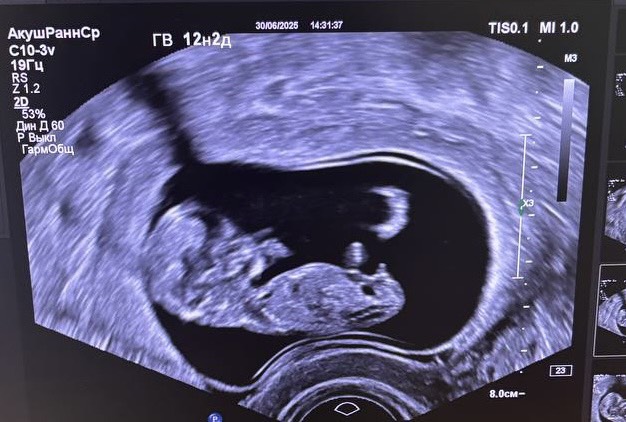

Первый скрининг🥳

Догнал по срокам

Ктр 5,5 см - 12,2 недели

Предлежание хориона уже не полностью перекрывает зев💪🏻